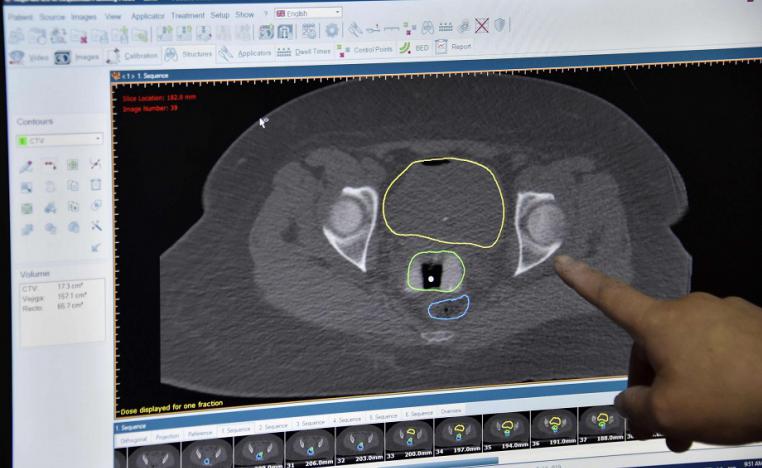

سرطان البروستاتا يستشرس على ذوي الوزن الزائد